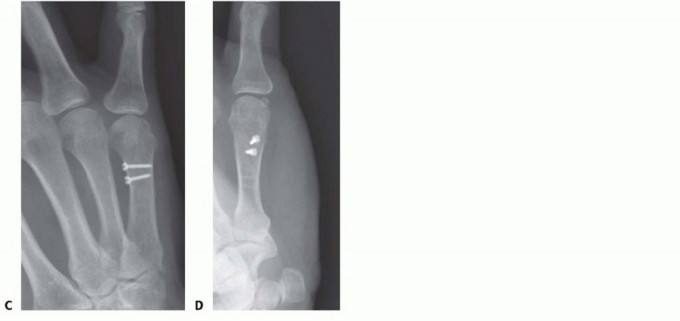

Once reduced, fixation can be achieved via crossed Kirschner wires or retrograde intramedullary pinning (the "bouquet" technique). However, the modern gold standard for minimally invasive fixation is the retrograde intramedullary headless compression screw. A small stab incision is made over the dorsal aspect of the flexed MCP joint. The entry portal is meticulously established in the articular "safe zone" of the metacarpal head—specifically the dorsal-ulnar or dorsal-radial collateral recess, strictly avoiding the central weight-bearing articular cartilage.

A guidewire is advanced down the medullary canal across the fracture site under fluoroscopic guidance. After confirming perfect rotational alignment and length, the canal is sequentially broached or drilled, and an appropriately sized headless compression screw is buried beneath the articular cartilage. This technique provides robust, load-sharing stability that allows for immediate, unrestricted active range of motion, vastly reducing the incidence of postoperative stiffness compared to traditional K-wire constructs.

Plate and Screw Fixation Execution

The application of hardware must adhere to strict biomechanical principles. For long oblique fractures, interfragmentary lag screws are the most biomechanically efficient method of achieving absolute stability. The technique requires drilling a gliding hole (e.g., 2.0mm or 2.4mm) in the near cortex, followed by a smaller thread hole (e.g., 1.5mm or 1.8mm) in the far cortex, utilizing a specialized drill guide. The near cortex is countersunk to prevent the screw head from acting as a stress riser or irritating the overlying tendon. As the screw is tightened, the fracture fragments are dynamically compressed together.

When a dorsal plate is required, it must be meticulously contoured to match the natural dorsal convexity of the metacarpal to prevent secondary displacement during screw insertion. For transverse fractures, the plate is applied in compression mode using eccentrically placed screws. For comminuted fractures, the plate functions as a bridge, bypassing the zone of comminution to maintain length and alignment without disturbing the fracture hematoma. Locking screws are utilized in osteoporotic bone or very short distal segments to prevent hardware pullout.

Clinical & Radiographic Imaging Archive